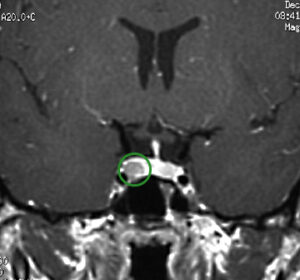

Normally, cortisol and ACTH levels fluctuate throughout the day, tending to be higher in the morning and lower in the late afternoon, evening and night. In patients with Cushing’s disease, this diurnal variation is typically lost and the overall quantity of cortisol produced by the adrenal glands is excessive. So endocrinologists over the years have come up with many ingenious ways to accurately measure the excess cortisol. Examples include collecting blood, 24 hour urine and late night salivary samples as well as doing sophisticated sampling of blood near the pituitary gland in the skull base (a procedure called inferior petrosal sinus sampling). In some patients with equivocal results, additional or repeat testing may be required before recommending surgery. It is ideal that an endocrinologist experienced in managing people with Cushing’s disease be in charge of the evaluation process for determining if a patient does or does not have CD.

After diagnostic confirmation of Cushing’s disease has been made, endonasal removal of the adenoma and preservation of the normal pituitary gland is the treatment of choice. When performed by an experienced pituitary surgery team, long-term remission rates average close to 80% and the risk of major surgical complications is very low, including a risk of new pituitary gland failure of less than 5%. The success rates are highest (typically over 90%) in patients with a clearly defined non-invasive microadenoma (less than 1 cm in diameter) as seen on MRI. For patients with invasive adenomas or those in which the adenoma is not visible on high-quality pituitary MRI with dynamic sequencing, remission rates are substantially lower (typically ranging from 40-70%).